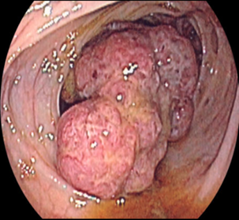

• Rektoromanoskopiya və ya fibrosiqmoidoskopiya- 75-80% diaqnoz qoyulur. Xarakterik 2-10 mm diametrli sarı rəngli düyünlər aşkar edilir.

Rektoromanoskopiya və ya fibrosiqmoidoskopiya - Xarakterik 2-10 mm diametrli sarı rəngli düyünlər aşkar edilir;